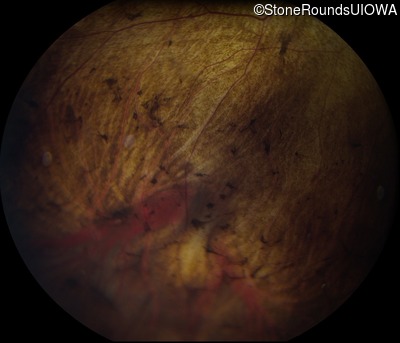

Fundus Photography - Right - 20/15 -2

Exemplar